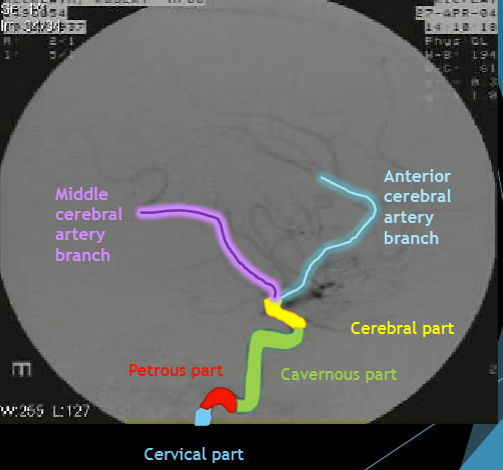

Please label the internal carotid artery (ICA)

Label the circle of willis

Please label the circle of willis